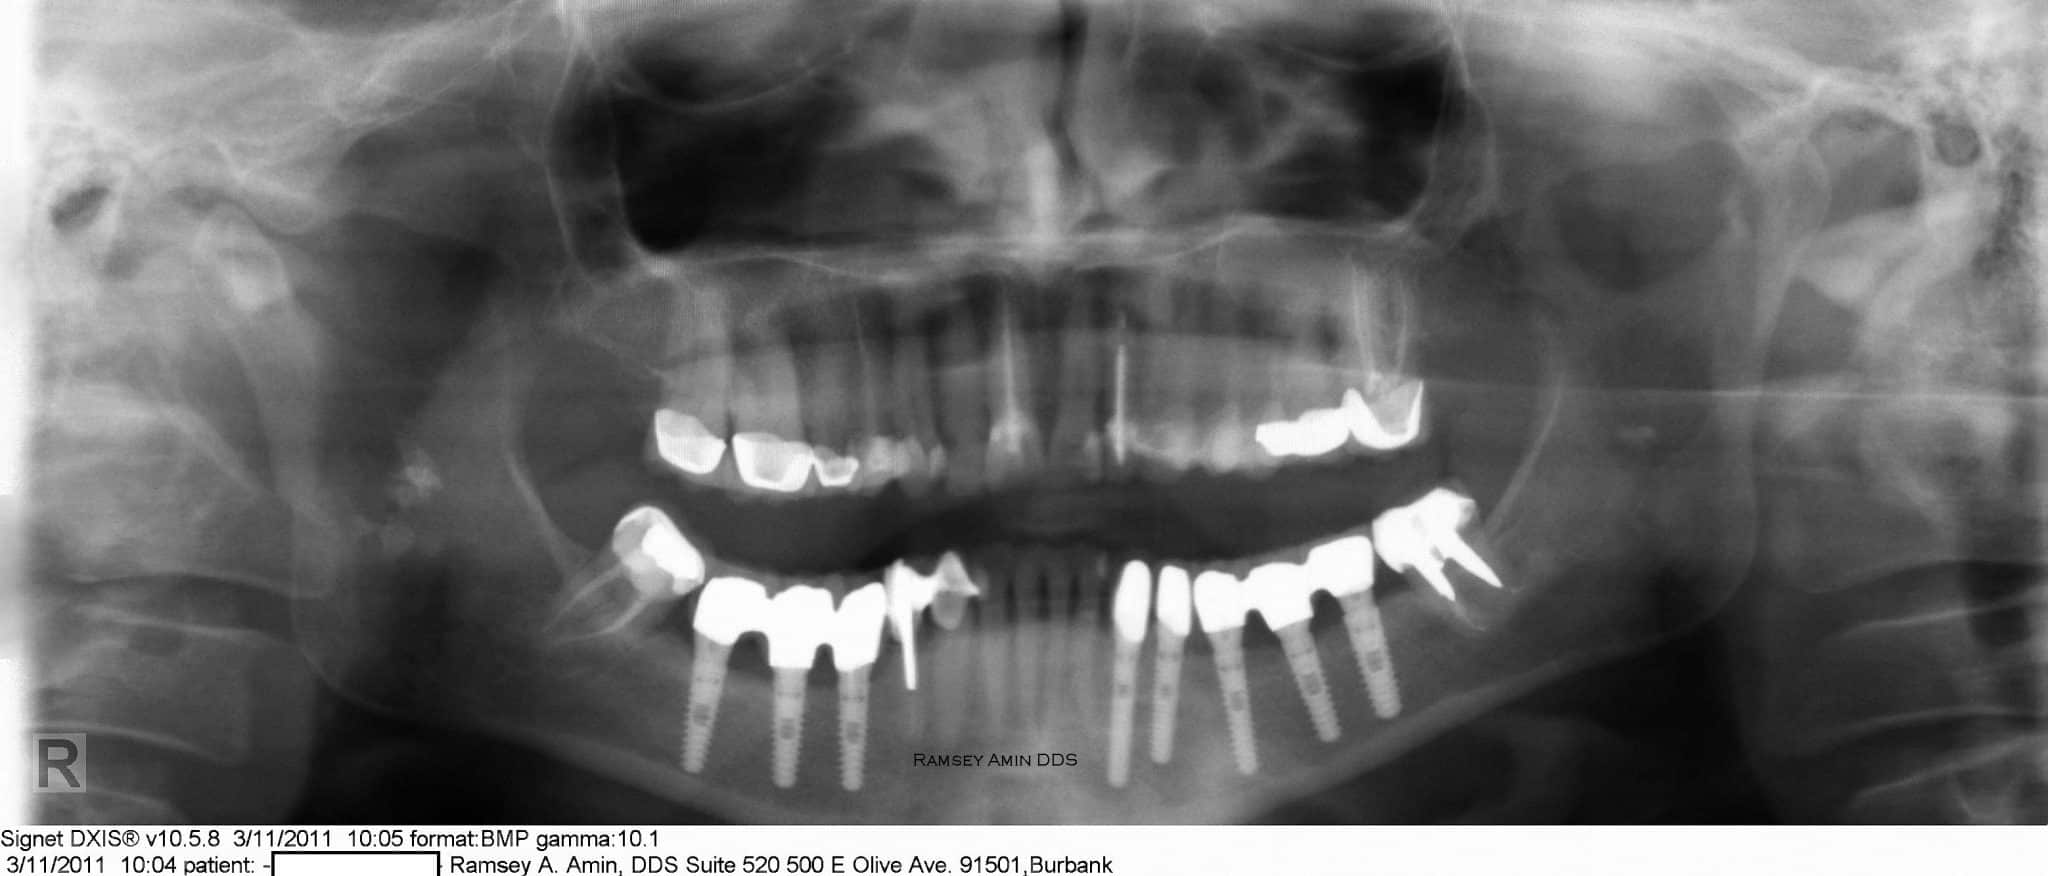

From burbankdentalimplants.com

AllOn4 Dental Implant Problems And Complications Dental Implant Complication The possible treatment options for implant failure include the replacement of a faulty implant right away with one with a larger. Frequent mechanical complications include abutment screw loosening, abutment fracture, and prosthesis fracture of both the veneer and the framework. Dental implants are an effective way of replacing lost or damaged adult teeth. It’s a procedure where your dentist places. Dental Implant Complication.